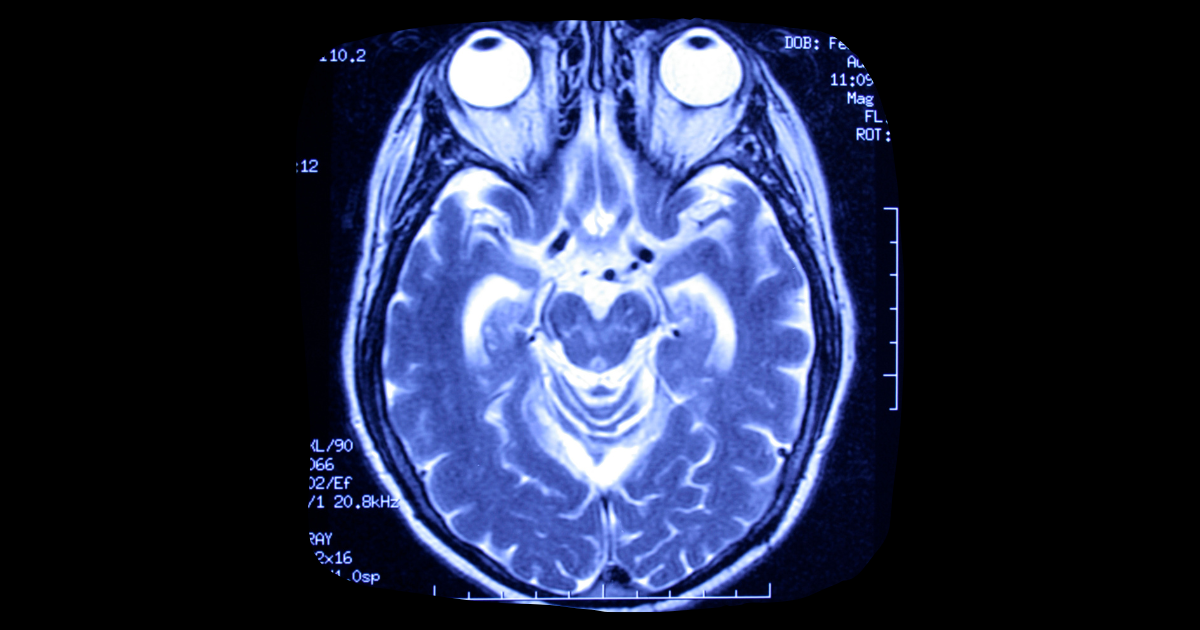

Yesterday’s Daily Beast report detailed just how hard it is to legally define death, which before 1959 was defined simply as the heart and lungs ceasing to function. But after French physicians discovered “coma dépassé,” which means “beyond a coma,” legal clarification was written allowing doctors and hospitals to complete organ donations from these types of patients in order to save other patients’ lives.

But what if brain death is reversible, or not 100 percent complete? Thaddeus Pope of the Mitchell Hamline School of Law says these conversations start to revolve around which lives are most valuable and that gets into stick territory.

Other doctors point out cases like that of a 4-year-old boy who went through a stunted kind of puberty even though he was on life support for 20 years. Puberty is a hormonal process controlled by the brain, giving credence to the idea that the person is still somewhat alive — or mostly dead, depending on how you look at it.